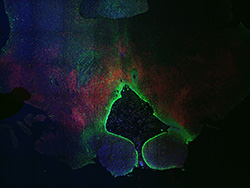

An anatomical analysis of the developing human midbrain from 6 post-conceptional weeks (PCW) to 22 PCW reveals increased tissue complexity, characterized by the emergence of dopaminergic nuclei, as highlighted by immunofluorescence analysis for tyrosine hydroxylase (TH).

13PCW

Merged

13PCW human midbrain